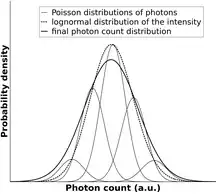

Because of the photon nature of X-rays, intensity measurements inevitably contain shot noise, which follows a Poisson distribution. Other types of noise, like detector noise or electrical noise can also contribute to fluctuations of the measured X-ray signal but do not provide information about the studied sample. In comparison, X-ray intensity changes arising from the alteration of attenuation carry important motion information. Statistical analysis of the data allows correction for the known noise sources to ascertain changes that result from movements within the sample or patient. The objective of kinetic imaging is to capture the motion information and represent it as a kinetic image.[1][2]

To calculate the attenuation values (E(D), Var(D), Err(E(D)) and Err(Var(D)) from the estimated photon counts (E(k),Var(k)), the distribution of the intensity probabilities should be estimated:

- If the distribution of attenuation can be estimated by a Gaussian distribution, the signal intensities (k, photon counts) follow a log-normal distribution.

- It is also assumed that the photon count values (k) are subject to Poisson distributed shot noise. In this calculation, the effect of instrument noise is ignored. However, if instrument noise contributes significantly to the measured fluctuations, the distribution of this noise must be determined and taken into account at this step.

The distribution of photon count probabilities can be used to estimate the expected value (E(D)) and the variance (Var(D)) of the attenuation:[1][2]